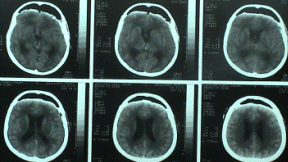

The patient came to clinic 11-November-2006  complaining of headache for 3 years with disturbed memory. The condition deteriorated and she got neck pain and vomiting attacks for 2 weeks and she came with dexametasone coverage. CT-scan performed 05-Noveber-2006  showed a suprachiasmatic mass in the left lateral and III ventricle with secondary acute hydrocephalus.

Pre and immediate postoperative CT-scan confirming radical resection of the mass and the Ommaya reservoir seen in place.